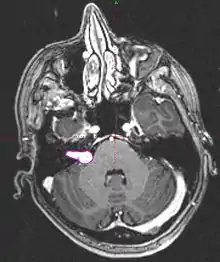

• Imaging: MRI with gadolinium can detect tumors as small as 1-2mm. Seen as an enhancing lesion “ice cream cone” in the region of internal acoustic canal or a “dumbbell” extending into the foramen magnum.